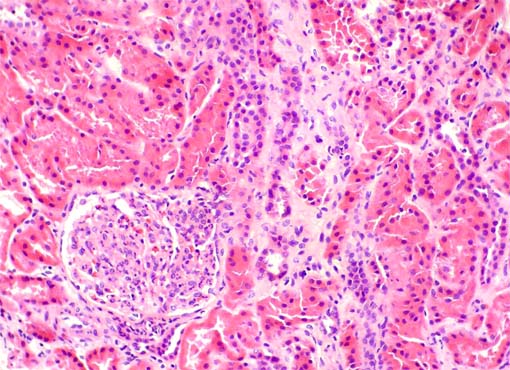

Figura 2.

H&E, X200.